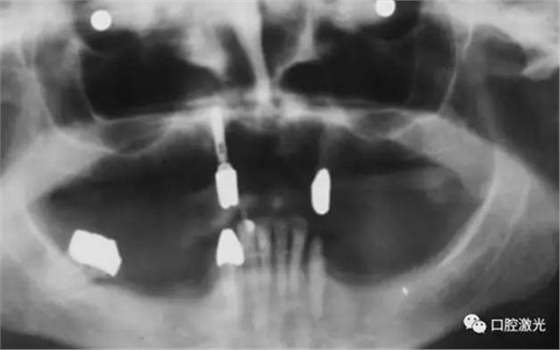

患者女性,43歲。在18年前在13位置上安裝種植體。整個上顎除23外,牙盡缺失。安裝種植體后,在種植體及23上固定套筒冠義齒。3年后患者發(fā)現(xiàn)刷牙時,臨近13有大量出血現(xiàn)象。通過探針檢查發(fā)現(xiàn)深度達6mm。

對患者實施局部麻醉,隨后在種植體位置進行翻瓣。利用塑料刮治器將肉芽組織清除干凈,并將翻瓣邊緣削薄。此時在種植體周圍可見明顯骨缺失。